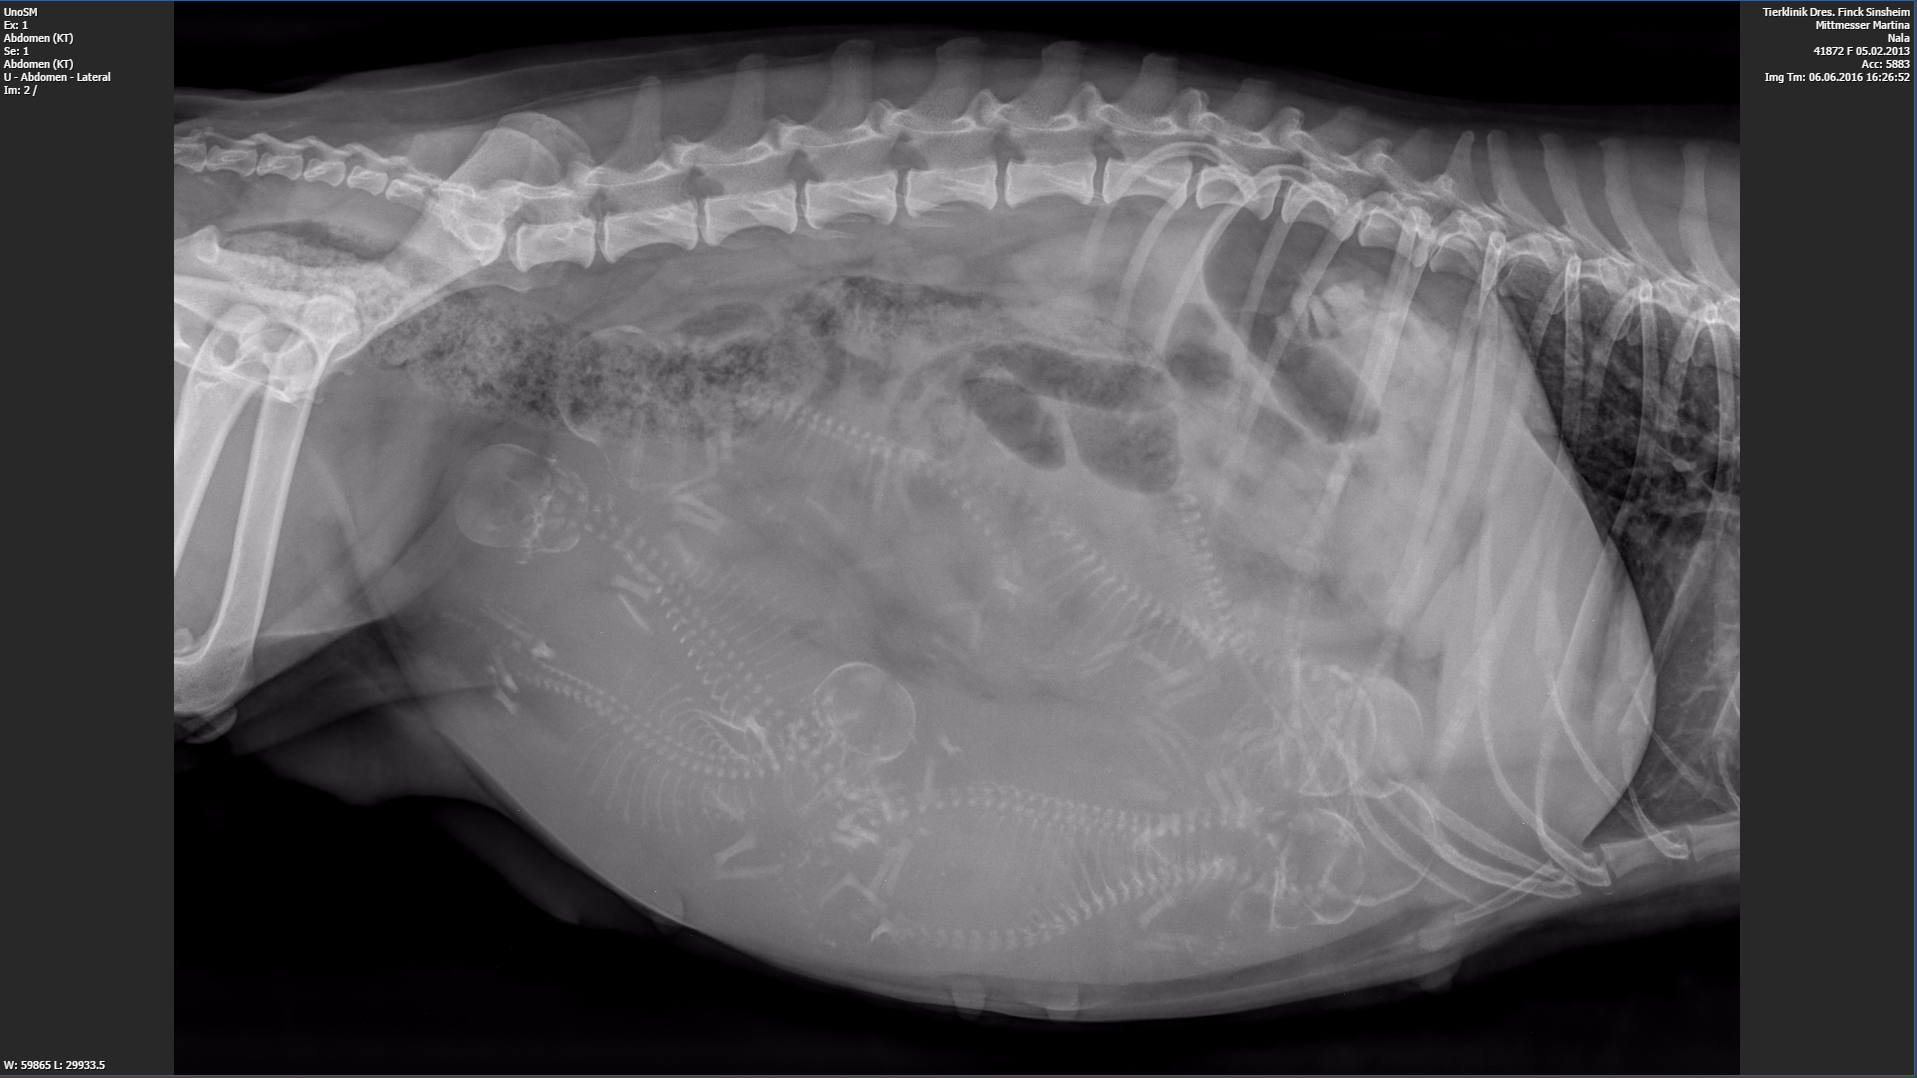

Bei unserer Großen ist es bald so weit. Die Kleinen müssten in den nächsten Tagen auf die Welt kommen.

Die Mama ist aber noch tiefenentspannt und lässt sich verwöhnen. Jetzt wird schon einmal die Wurfbox beschnuppert. Sieben Welpen werden es sein, da wird die Mama ganz schön viel zu tun haben. Jetzt aber erstmal noch schön entspannen und graulen lassen bevor die Rasselbande schlaflose Nächte bringt 🙂